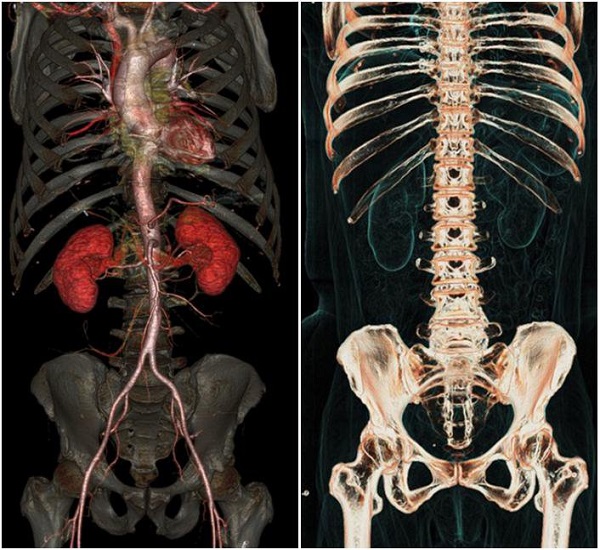

این روش توموگرافی رایانهای اشعه ایکس نیز نامیده میشود که اغلب در بیمارستان برای مشاهده تومورها، شکستگی استخوان و خونریزی داخلی استفاده میشود.

عروق، روده، قلب، مغز، استخوانها با جزئیات منحصربفردی به تصویر کشیده میشوند.

اسکنر GE برای بیمارانی که از ضربانساز قلبی یا ایمپلنتهای فلزی در داخل بدن استفاده میکنند، کاملا ایمن و بی خطر است.